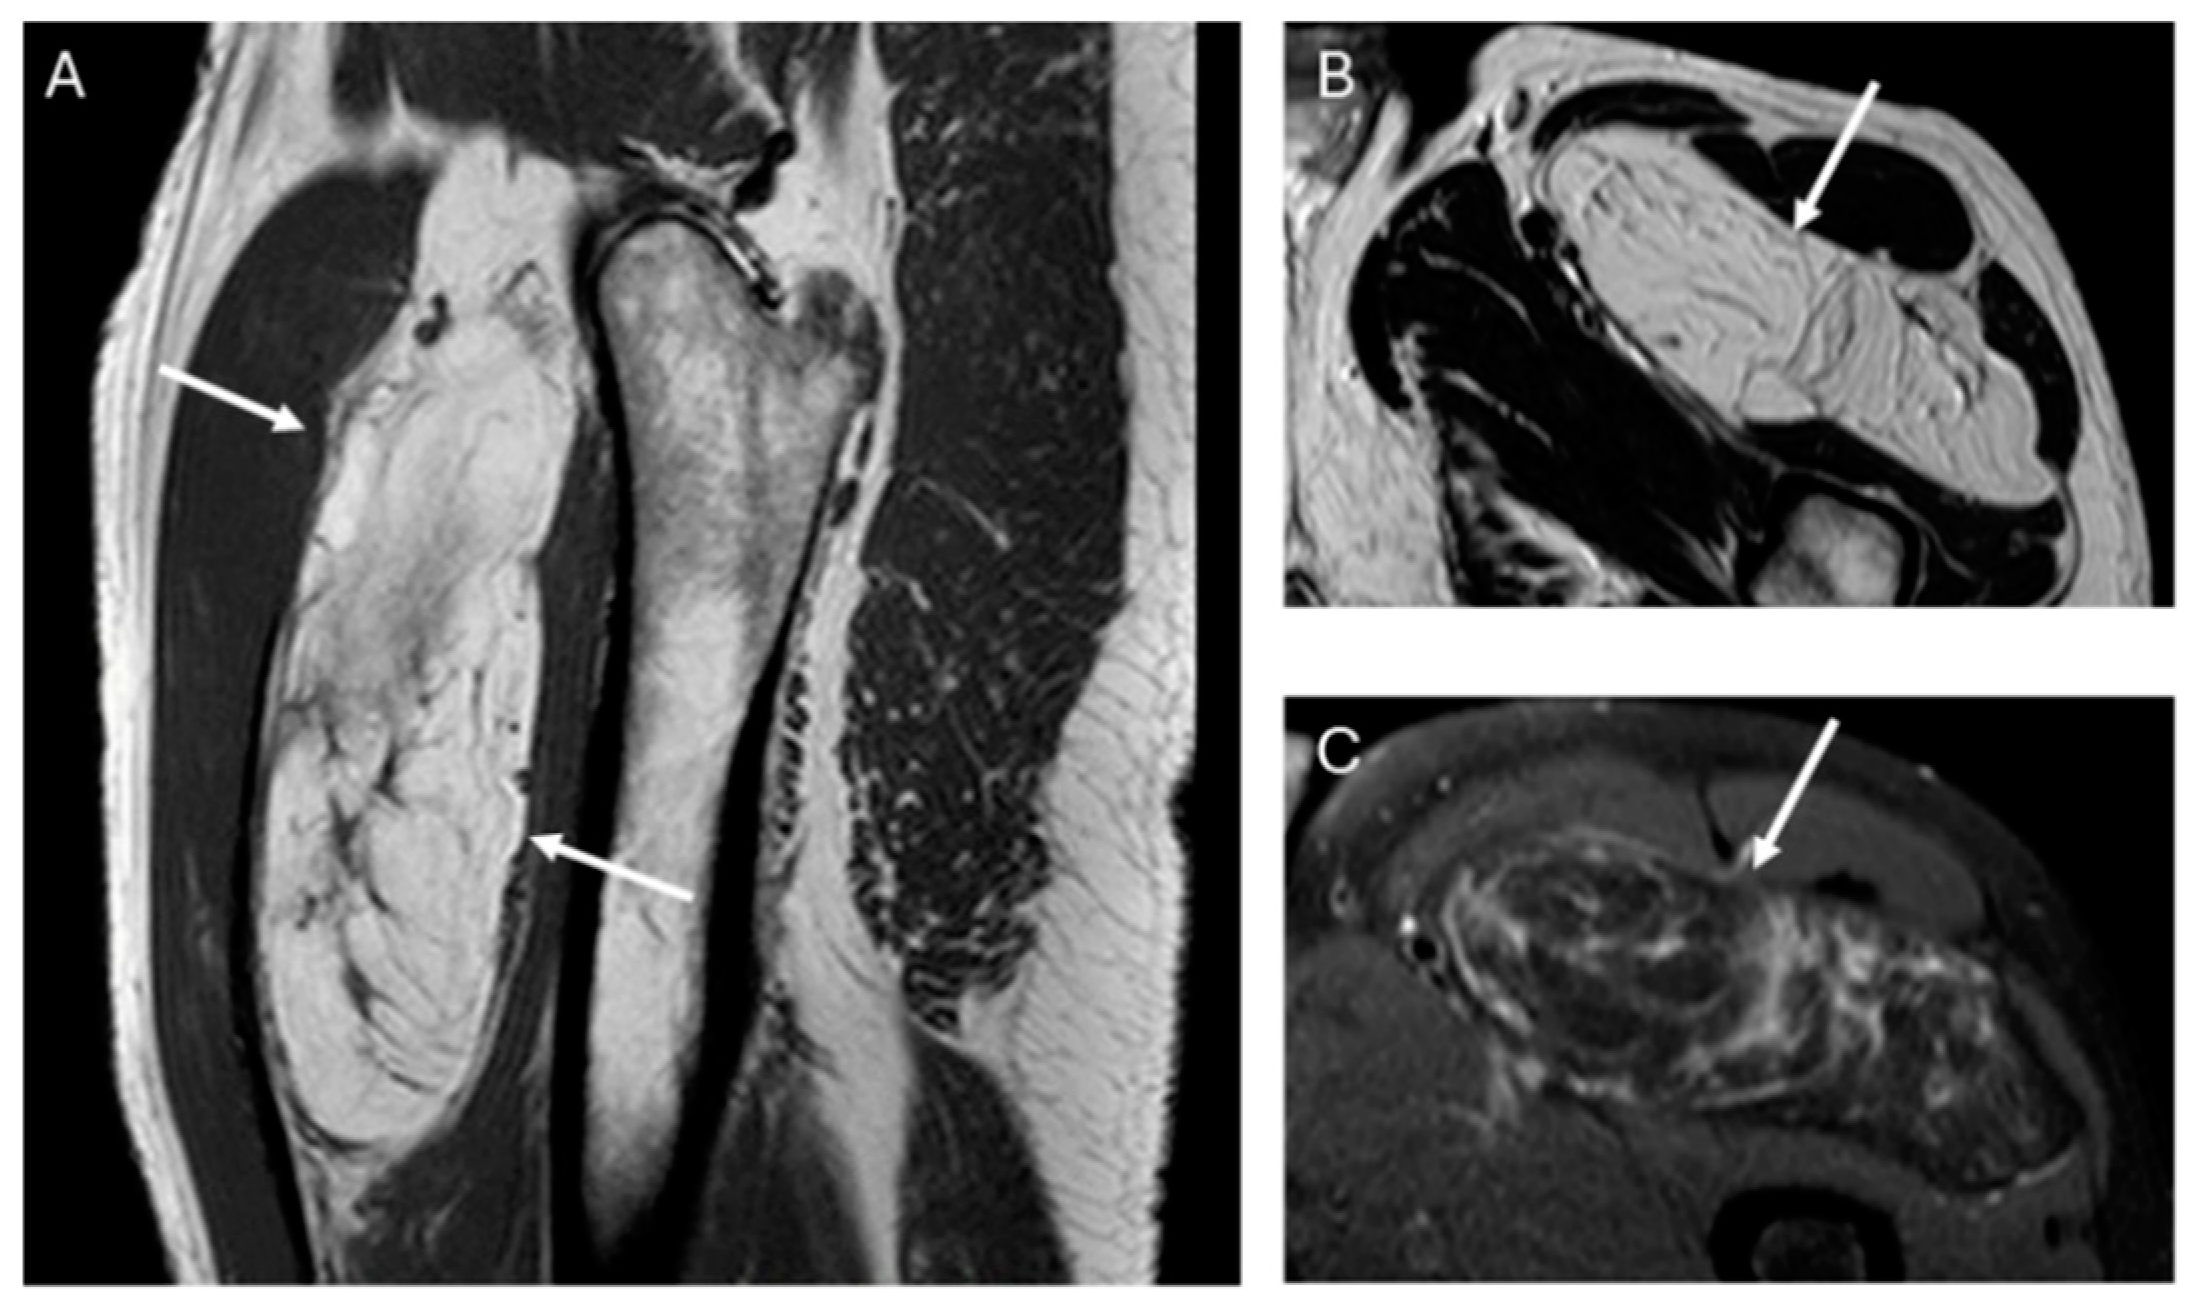

Fifty-four of the 59 lipomas had not septa or septa < 2 mm, while nineteen of 20 ALT had septa and these were ≥2 mm in 38%, (p value = 0.001) (Figure 2).

The presence and thickness of septa show significant differences between lipomas and ALTs. This one agrees with the findings of Kransdorf and Hosono, where the septa were thick and irregular in ALT/WDL and thin in lipoma [12,16]. Similarly, Brisson observed that lipomas were isointense to subcutaneous fat and may contain a few thin septa [17]. In our series, the absence of septa indicates lipoma and septa ≥ 2 mm is suggested of ALT. Septa < 2 mm can be indicative of either lipoma or ALTs (Figure 5).

Figure 2. Sagittal T1W (A) and axial T2W (B) and DP SPAIR (C) MR images with a heterogeneous lipomatous mass (arrows) in the anterior compartment of the left thigh. The final diagnosis was atypical lipomatous tumor (ALT) confirmed as MDM2 positive.